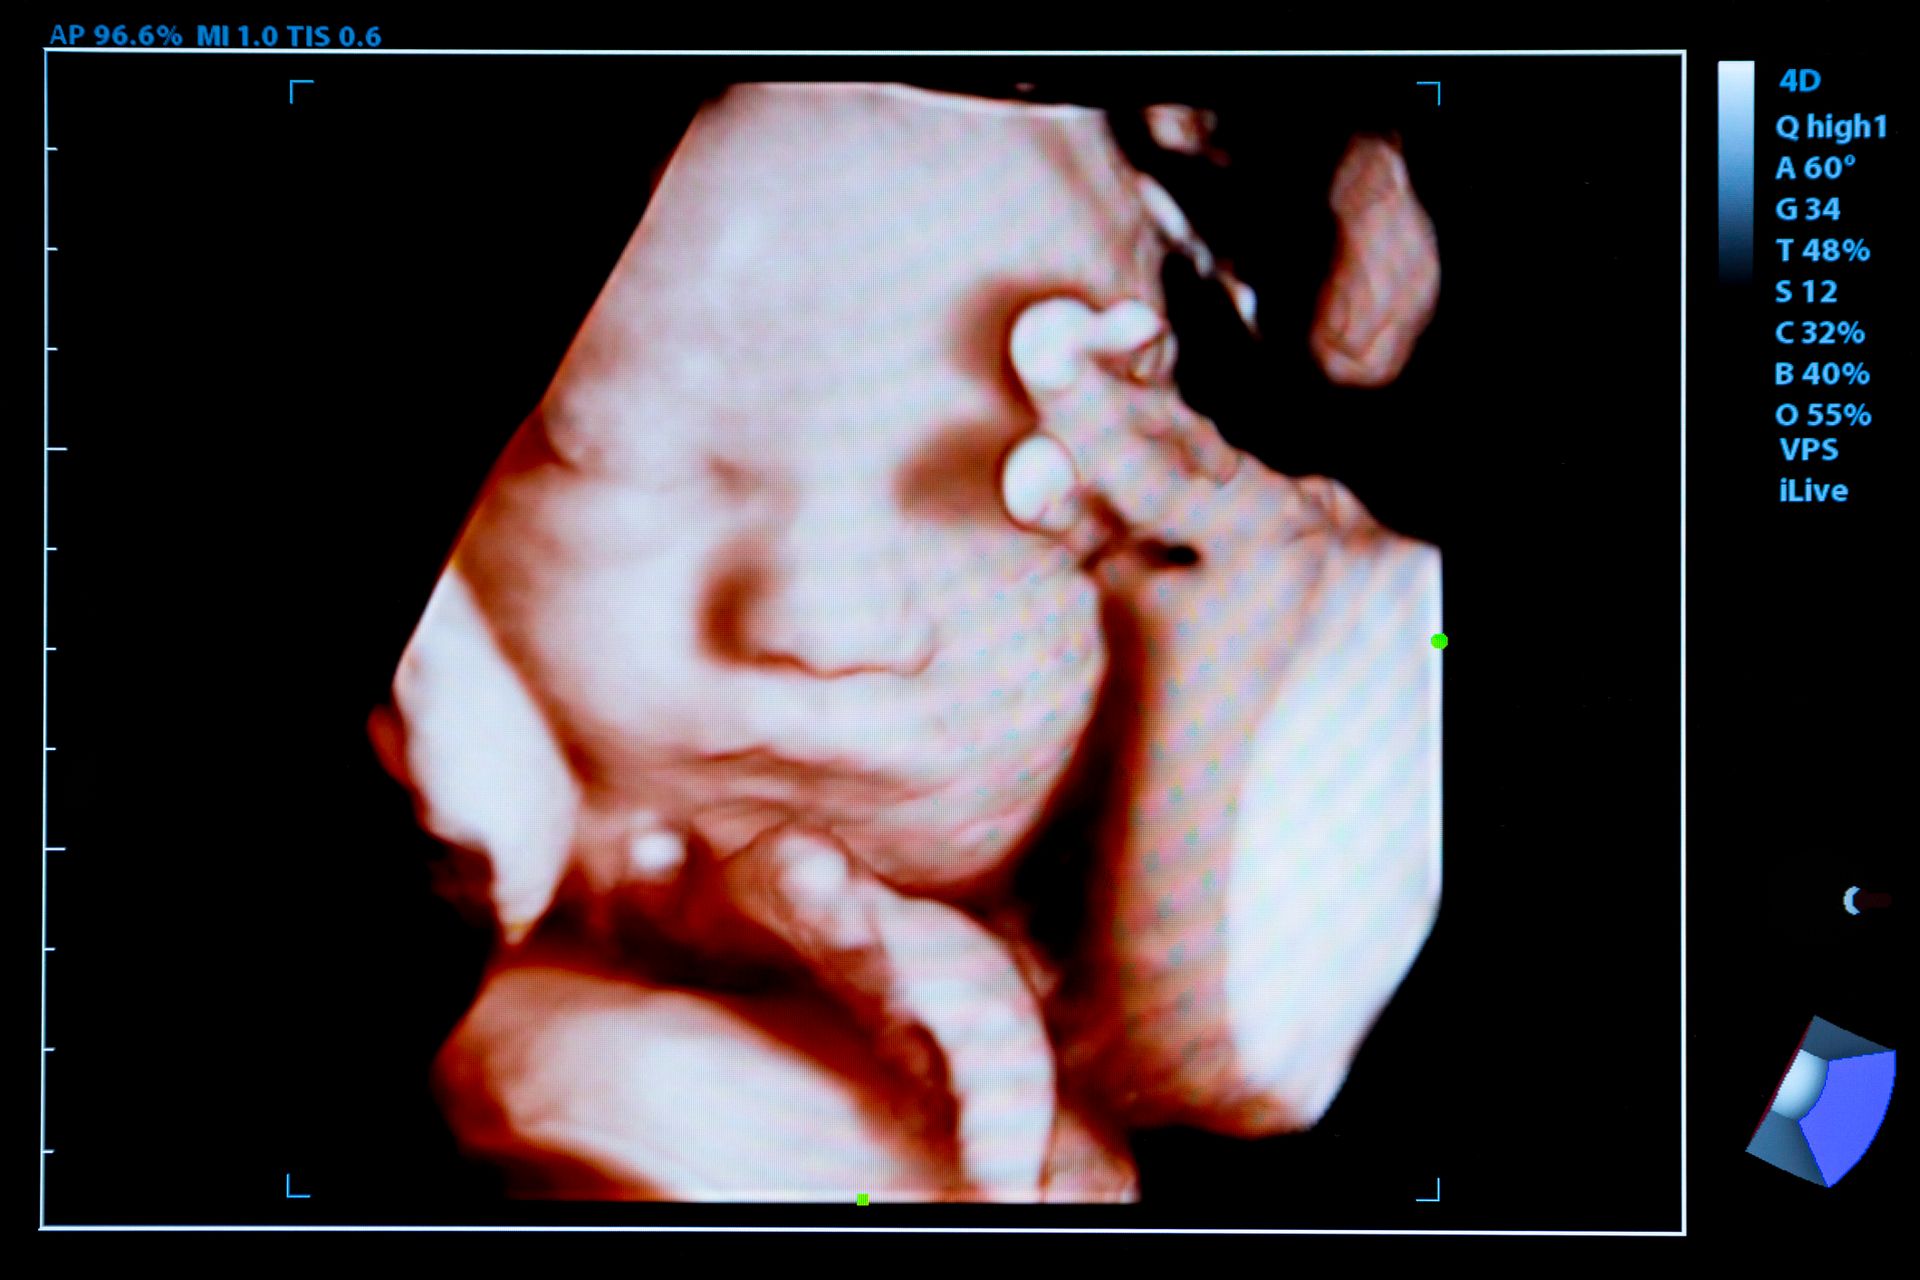

Il dottor Gianni Pirisi è un medico chirurgo specializzato in ostetricia e ginecologia, specialista in diagnostica ecografica prenatale ed ecografie 3D e 4D.

Lo studio che presiede è specializzato nella diagnostica prenatale ed è dotato delle più moderne apparecchiature, al fine di espletare con maggiore professionalità prestazioni mediche relative all'ecografia endovaginale, l'amniocentesi, l'ecografia 3D e 4D, ecografia ostetrica-ginecologica e diagnostica ecografica prenatale.